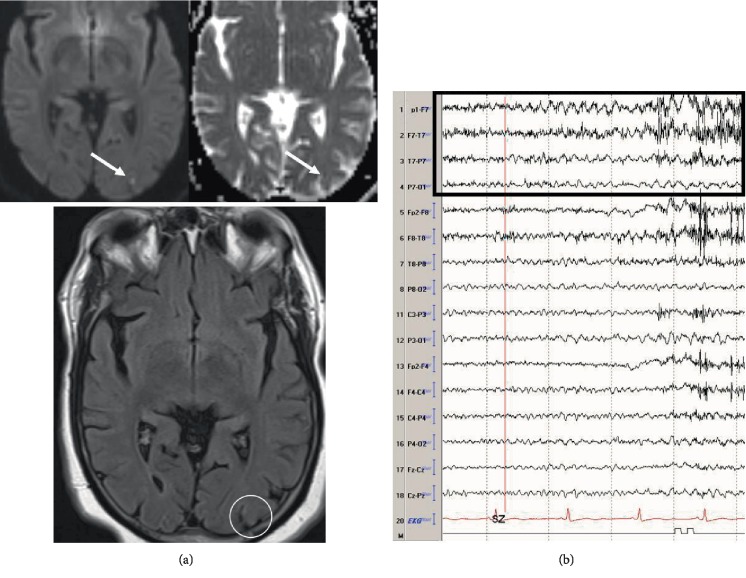

Purpose: Seizure is a well-recognized complication of both remote and acute ischemic strokes. Predictors of seizure recurrence and epilepsy in patients with ischemic stroke who develop acute symptomatic seizures (ASyS) on continuous electroencephalography (cEEG) have not been well studied.

Methods: We present a five-year retrospective study of acute and remote ischemic stroke patients who developed ASyS on cEEG. We then identified risk factors for the development of seizure recurrence.

Results: Sixty-five patients with ischemic stroke and ASyS were identified and reviewed. All ASyS were noted to be nonconvulsive seizures. Clinical recurrence of seizures was identified in 19 of these patients (29.2%) at follow-up. Rate of seizure recurrence was higher in remote ischemic stroke patients (84.2%), compared to acute ischemic stroke patients (15.8%, p = 0.0116, OR 0.17, 95% CI 0.049-0.65). Sharp waves/spikes on follow-up EEG significantly correlated with seizure recurrence (p = 0.006, OR 0, 95% CI 0-0.3926). Patients discharged on ≥3 antiepileptic drugs (AEDs) were at a higher risk of having seizure recurrence (p = 0.0015, OR 0.05, 95% CI 0.0089-0.37).

Conclusion: We identified risk factors of seizure recurrence in patients with ASyS as remote ischemic stroke, requiring multiple AEDs, and the presence of sharp waves on follow-up EEG. This study highlights the usefulness of cEEG in evaluating patients with acute or remote strokes.